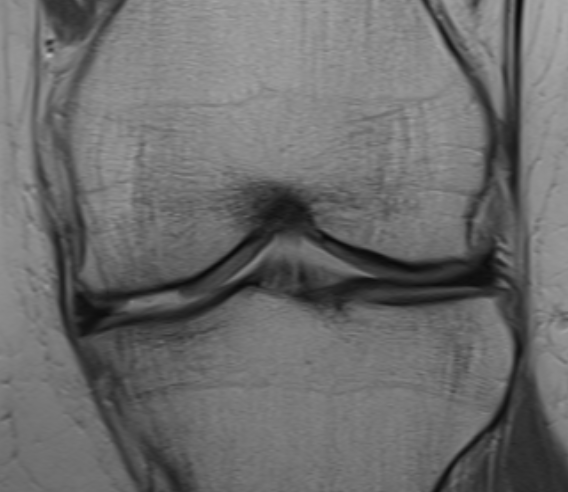

MRI

Chondral defect

Osteochondral defect